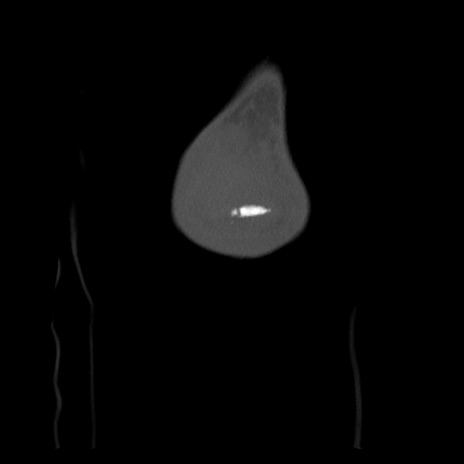

右膝関節CT

矢状断像